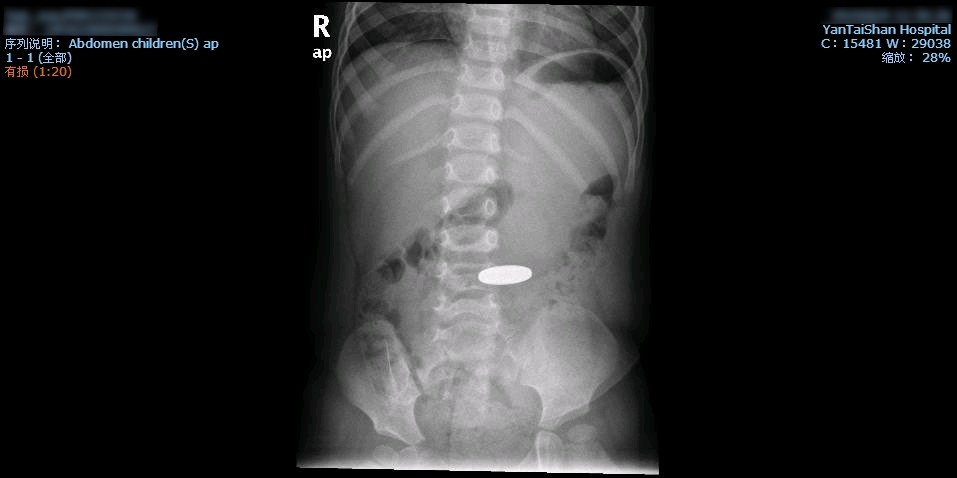

童童误吞硬币当日,家长带着他到当地医院就诊,透视检查发现,腹部偏右位置可以看到一个类圆形致密影,应为吞下的1元硬币,当地医院没有儿童电子胃镜,医生建议饮食促排。3天过去了,这枚硬币仍未排出,童童再到医院接受腹部透视检查,金属影的位置移到了中腹部。又过了5天,硬币还是没有排出,家长带着童童到当地的另外一家医院就诊,复查X线片,提示硬币仍在中腹部。再过了12天,硬币依旧没有排出,情急之下,家长带着童童来到了烟台山医院儿科就诊,复查X线片,提示硬币的位置在中下腹。

硬币到底是在胃里还是在肠道里?如果在胃里,为何位置偏低?如果已经进入肠道,为何持续20天都不能排出?烟台山医院儿科对此进行了全科讨论,认为异物在消化道内停留时间较长而未能自行排出,硬币还在胃里的可能性较大。在征得家长同意后,决定为童童做儿童无痛电子胃镜检查。